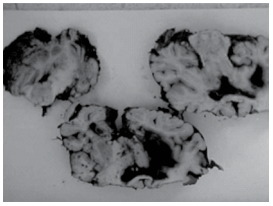

Indivíduo andando de moto sem capacete sofreu acidente de trânsito, foi arremessado em via pública, com afundamento do crânio e óbito por trauma cranioencefálico. A figura mostra cortes do encéfalo durante a necropsia.

É correto afirmar que

É correto afirmar que